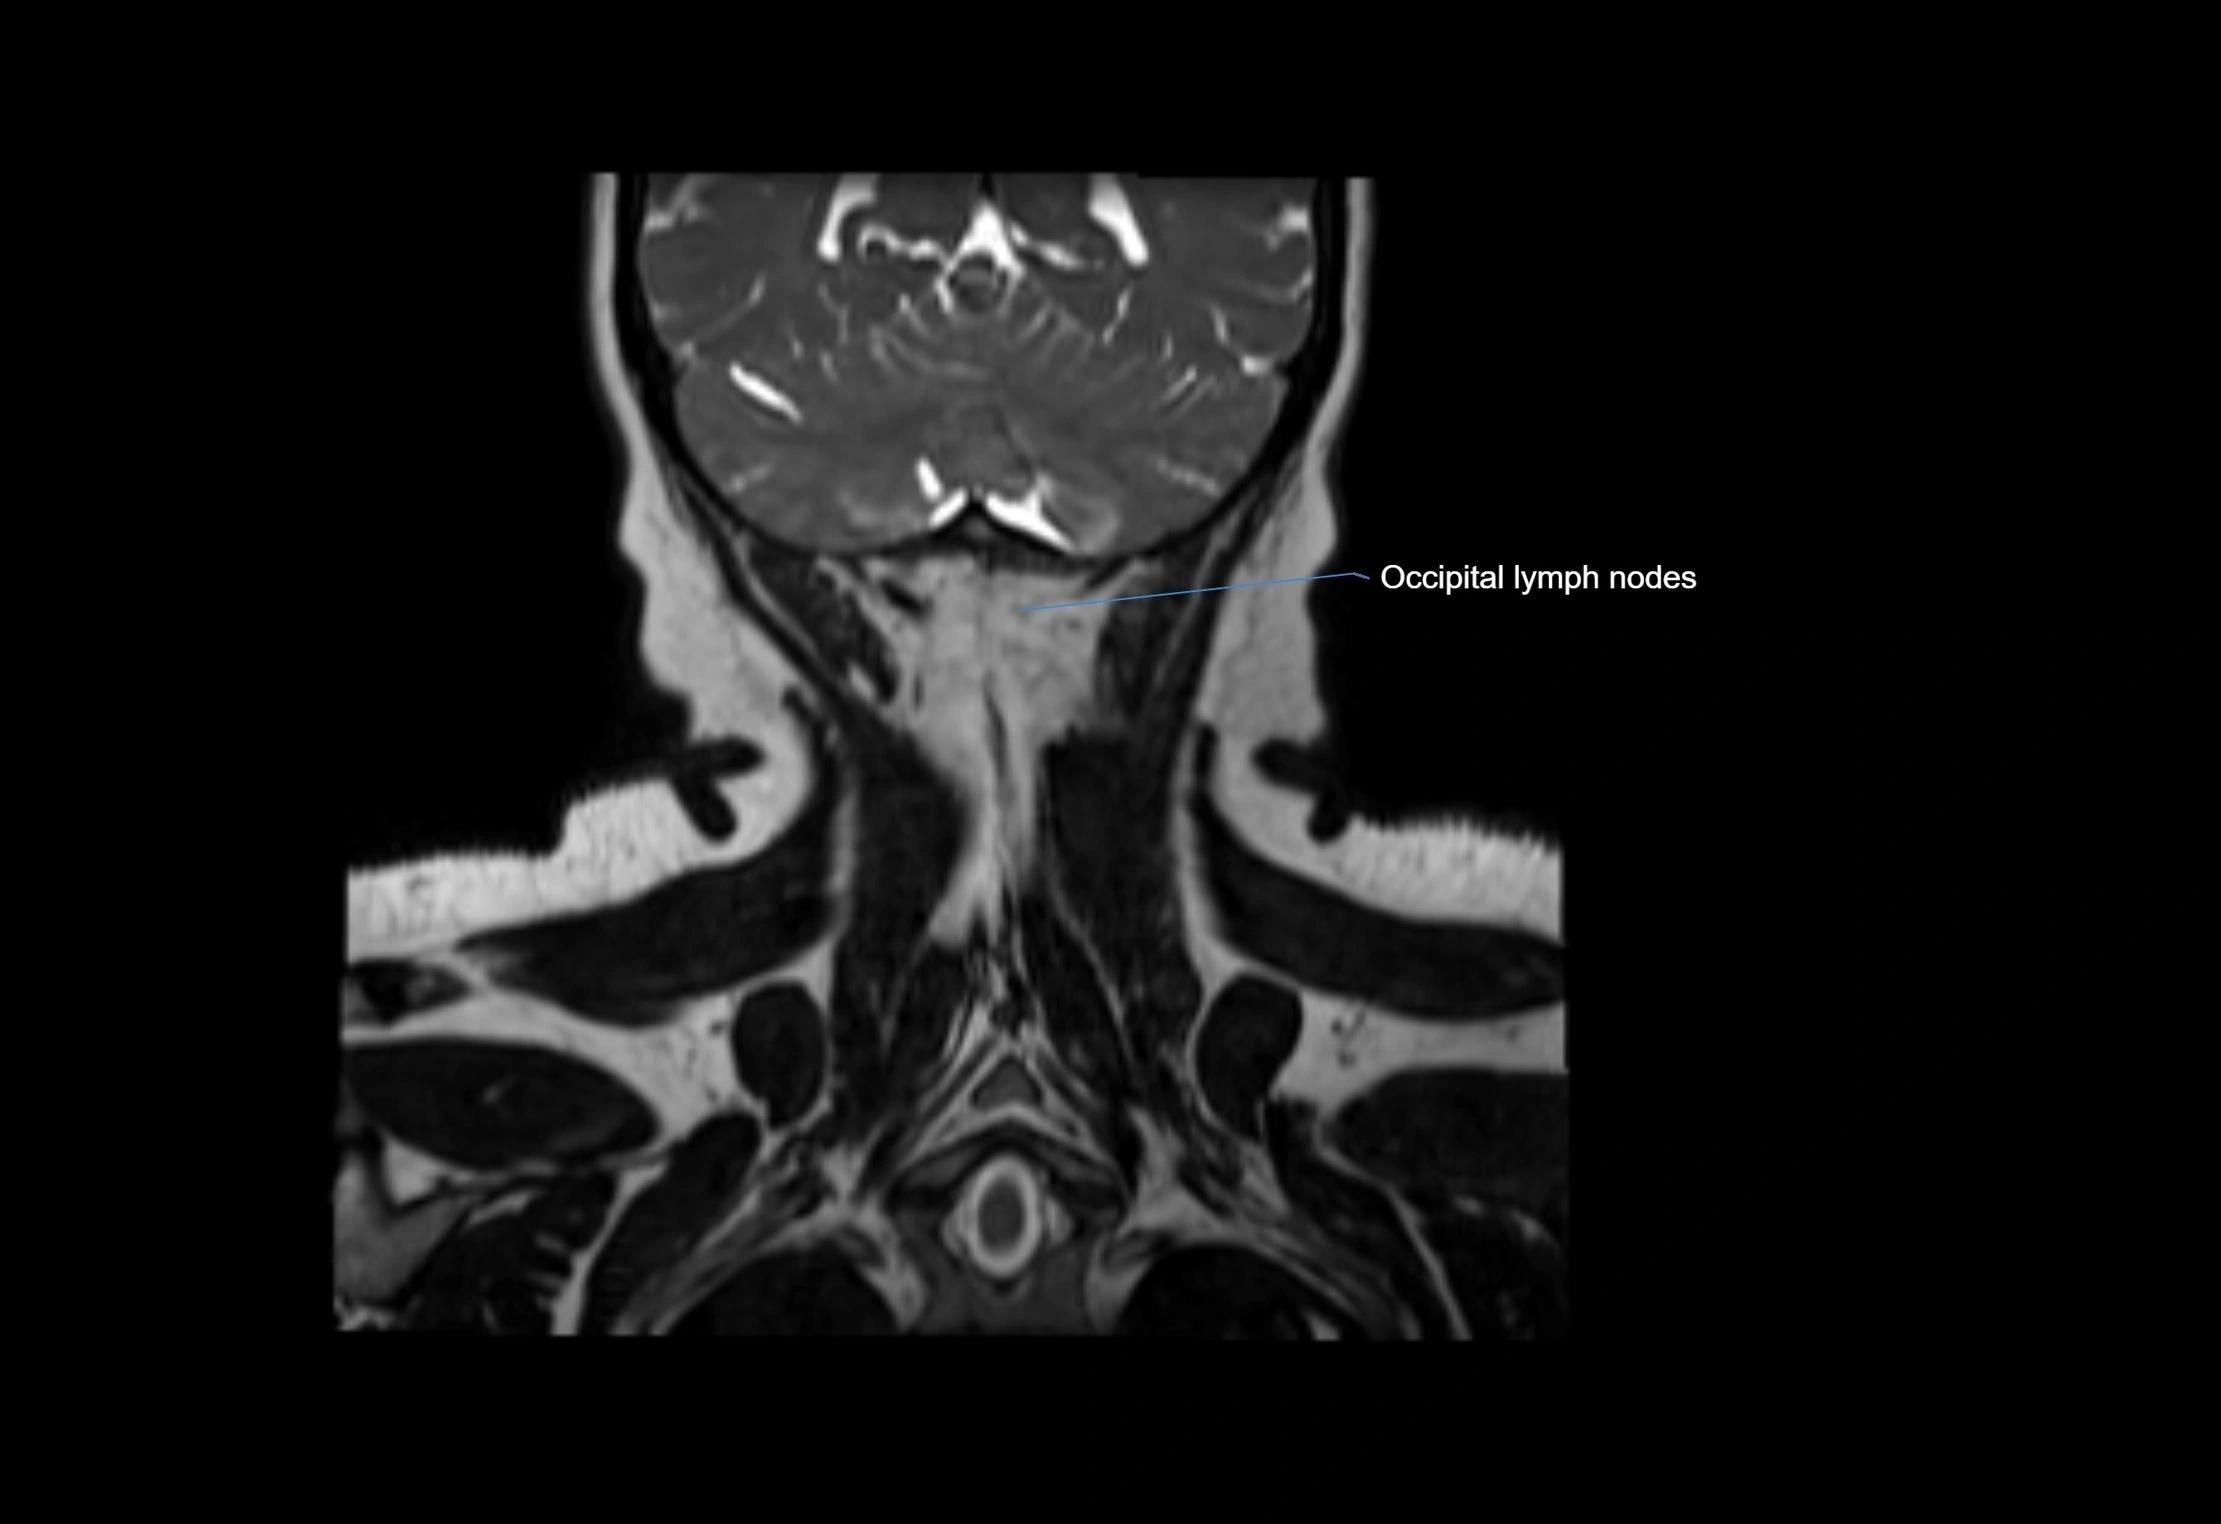

Accessory lymph nodes are small, secondary lymph nodes located along the main facial and cervical lymphatic chains, often adjacent to primary lymph nodes, such as preauricular, submandibular, or occipital nodes. They are typically less than 5 mm in diameter, embedded within subcutaneous fat or connective tissue, and may be variable in number and location. These nodes provide additional filtration and immune surveillance for lymph collected from the face, scalp, and neck regions. Accessory lymph nodes are usually non-palpable in healthy individuals but may enlarge in response to infection, inflammation, or metastasis, making them clinically significant.

Location

• Found along primary lymph node chains, including preauricular, submandibular, parotid, and occipital regions

• Embedded in subcutaneous fat or superficial fascia, often lateral or posterior to primary nodes

• Variable in number; may occur unilaterally or bilaterally, depending on individual anatomy

MRI images